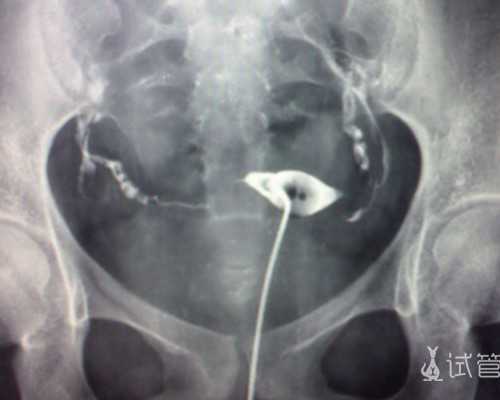

香港验血的原理:当宝宝在母体里面逐渐发育的时候,其自身的DNA会慢慢渗入妈妈的血液里。利用基因工程的技术检测妈妈的血液里是否含有Y染色体。大家都知道男孩和女孩的染色体是不一样的,女性是XX,男性是XY。如果从妈妈的血液提取的DNA检测到Y染色体,那就可以判断那一定不是女性的基因,那么胎儿就是男孩,反之没有查到Y染色体,那么胎儿就是女孩。

香港验血是通过抽取孕妇手臂静脉血,检测孕妇血液当中是否存在Y染色体,如果检测到Y染色体则是男胎,没有检测到Y染色体则是女胎。准确率高达99.9%,报告只需一个工作日出结果。香港验血可以说是最早期并且准确最高的检测。